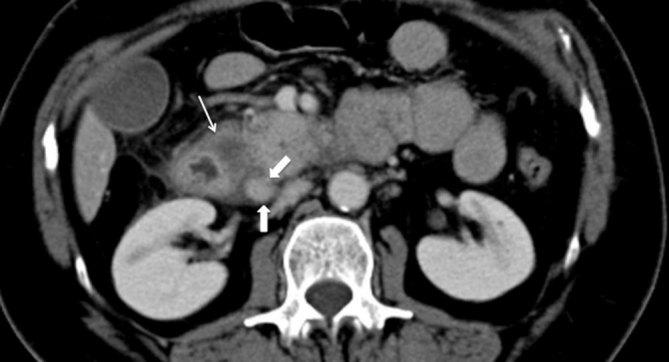

Cystic dystrophy of the duodenal wall in heterotopic pancreas, recently described as paraduodenal pancreatitis, is a rare condition characterized by multiple cysts or pseudocysts located in the submucosa or muscularis propria of a thickened duodenal wall. They result from multiple episodes of obstruction of the small ducts in aberrant pancreatic islets. Cystic dystrophy of the duodenal wall in heterotopic pancreas usually affects alcoholic males, but here we present the case of a female without a history of alcohol abuse who was referred to our emergency department with abdominal pain and vomiting. She was treated by a pancreas-preserving surgical approach, thanks to a proper pre-operative differential diagnosis. Even though differentiating this benign condition from pancreatic cancer is a challenge, some characteristic findings on multidetector CT scan and MRI/MR cholangiopancreatography, such as a thickened duodenal wall containing cysts and sheet-like tissues in the pancreaticoduodenal groove, could lead to the correct diagnosis.

十二指肠壁囊肿性营养不良合并异位胰腺,最近被描述为十二指肠旁胰腺炎,是一种罕见的病症,其特征是在增厚的十二指肠壁的黏膜下层或固有肌层中存在多个囊肿或假性囊肿。它们是由异常胰岛中小导管的多次梗阻引起的。十二指肠壁囊肿性营养不良合并异位胰腺通常影响男性酗酒者,但在此我们报告一例无酗酒史的女性病例,该女性因腹痛和呕吐被转诊至我们的急诊科。由于术前进行了恰当的鉴别诊断,她接受了保留胰腺的手术治疗。尽管将这种良性病症与胰腺癌区分开来具有挑战性,但多排CT扫描和MRI/MR胰胆管造影的一些特征性表现,如十二指肠壁增厚并伴有囊肿以及胰十二指肠沟内的片状组织,可有助于做出正确诊断。